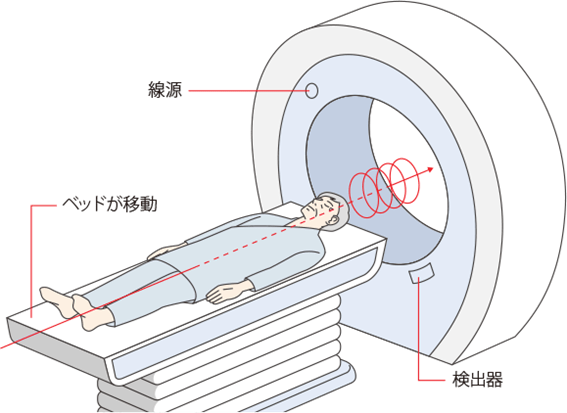

CTの撮り方

人間を一本の円柱と考えると、CTを実際に撮るときには輪切りにした方が簡単で、効率がよくなります。従ってCTを撮るときには移動可能なベッドに横たわり、大きな輪の中に入っていきます。

この輪の内部にX線の線源(X線を発射する装置)と検出器があり、ちょうど体をはさむようになっています。撮影のときは線源がX線を発射し、体を通したX線を検出器が受け取りながらぐるりとまわります。(実際にはまわっている検出器は見えません)

検出器が1回まわるごとに一枚の体の輪切りの像ができます。ベッドを少しずつ移動しながら、これを繰り返すことで体全体の輪切りの像を見ることができます。

通常、診察室で見せられるCTの写真はこれらの像を通常のフィルムに出力したものです。胸部のCTの場合は足元から見た形で撮影しているので、向かって左が自分の体の右側になります。寝転がっている自分をもう一人の自分が足元から眺めていると考えてください。